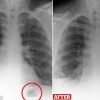

폐 속 암덩어리?…알고보니 40년 전 삼킨 장난감